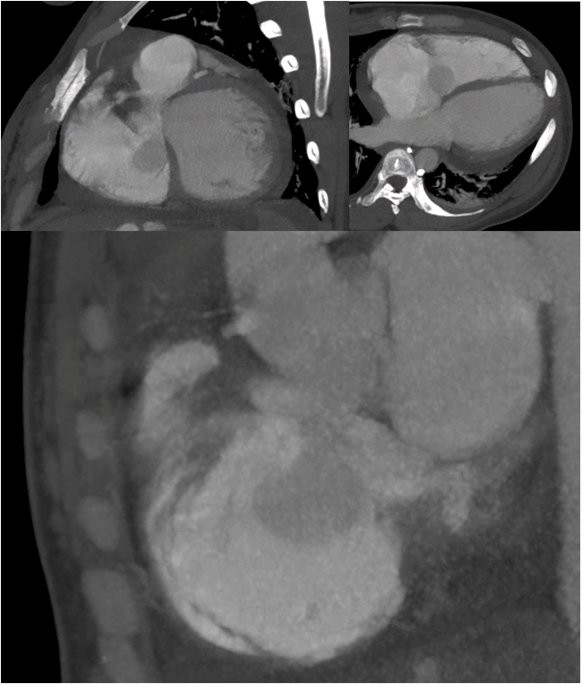

Given the clinical presentation and initial findings, the patient was provisionally diagnosed with acute decompensated heart failure, with peripartum cardiomyopathy as the leading differential. Computed tomography angiography was performed to exclude pulmonary embolism, which was ruled out. However, the scan revealed signs of pulmonary hypertension, right ventricular strain, and abdominal ascites.

Figure 3: Nongated chest computed tomography angiography (CTA). Axial and coronal views demonstrate a prominent outpouching from the noncoronary sinus of Valsalva projecting into the right atrium, consistent with aneurysmal rupture. A region of swirling contrast with similar attenuation to the ascending aorta is visualized within the right atrium, indicative of a significant left-to-right shunt. Although limited by motion artifact and non-gated acquisition, the study provided key diagnostic clues supporting the diagnosis of ruptured sinus of Valsalva aneurysm (SOVAR).

Cardiac computed tomography angiography can also be a valuable tool in the diagnosis and management of sinus of Valsalva aneurysm rupture. This patient population is typically young and often at low to intermediate risk for obstructive coronary artery disease. In such cases, cCTA can reliably exclude coronary disease, potentially avoiding the need for invasive coronary angiography—particularly when the involved sinus corresponds to the origin of a coronary artery. Moreover, engagement of the coronary ostia during angiography may be technically challenging due to anatomical distortion and structural injury. While surgical repair remains the standard of care, emerging transcatheter, nonsurgical alternatives have been proposed (Latzman et al., 2006; Weinreich et al., 2015). In this context, cCTA can serve as an accurate tool for preprocedural planning. In our patient, SOVAR evaluation with chest CTA was partially limited by motion artifact at the level of the aortic root and suboptimal bolus timing for aortic evaluation. Nevertheless, it provided key diagnostic clues. Notably, there was evidence of negative contrast and swirling flow within the right atrium, largely isointense to the ascending aorta, consistent with a left-to-right shunt. Additionally, an aneurysmal outpouching of the non-coronary sinus projecting into the right atrium was clearly visualized.